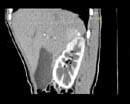

问题 女,35岁,上腹部隐痛不适伴消瘦1月,胃镜提示胃癌,CT扫描如图所示:右侧肾上腺区可见一占位性病灶,应诊断为 ( )

选项 A、右肾上腺嗜铬细胞瘤 B、右肾上腺错构瘤 C、右肾上腺腺癌 D、右肾上腺转移瘤 E、右肾上腺腺瘤

答案 D